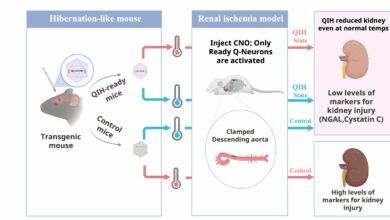

Estudo descobre que induzir estado de hibernação em camundongos pode proteger seus órgãos durante cirurgia cardíaca

Resumo do experimento: A parada circulatória é necessária em muitas cirurgias cardíacas e aórticas para que os cirurgiões possam reparar…